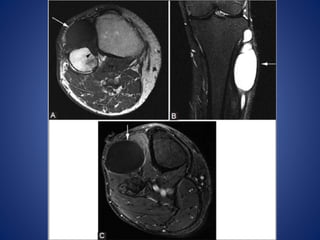

• #35 Intramuscular hemangioma. A 54-year-old female with knee mass and pain. (A) Sagittal T2W fat-saturated and (B) axial T1W fat-saturated post-contrast images show a lobulated enhancing cystic mass (arrows) in the vastus medialis

• #36 Lymphatic malformation. A 23-year-old female with palpable medial knee mass. (A) Coronal T1W image shows multilobulated cystic lesion (arrows) in the medial aspect of the knee that is isointense and hyperintense to muscle. (B) Axial fat-suppressed T2W image shows fluid-fluid levels (arrow) in this multicystic lesion

• #38 Schwannoma. A 38-year-old male with knee pain. Axial (A) T1W and (B) T2W fat-suppressed images show T2-hyperintense lesion (arrows) in the lateral soft tissue of the knee. (C) Coronal PDW image confirms that the mass (arrow) arises from common peroneal nerve (arrowheads).